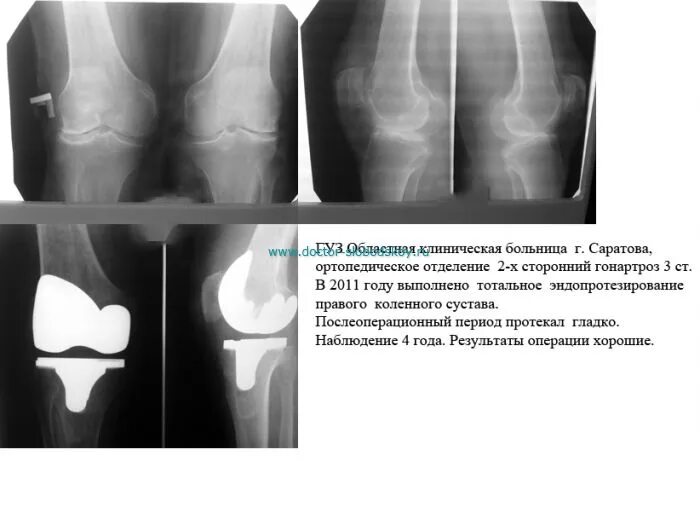

Форум после эндопротезирования коленного сустава